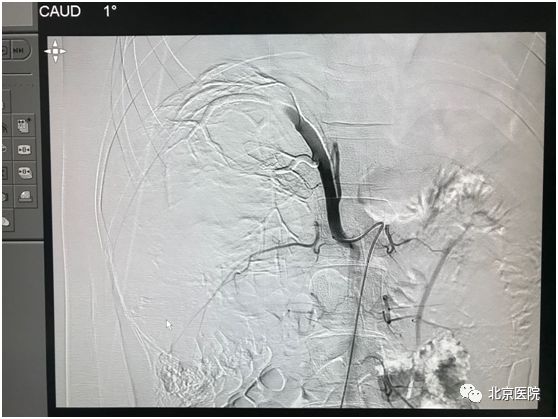

栓塞后可见肿瘤供血主干呈枯树枝样

1970年,Wholey首次将肾动脉栓塞术应用于临床,以控制肾癌术中出血。这一技术具有以下优点:1、减少术中出血,提高手术切除率。2、促进机体肿瘤免疫调控过程,选择性肾动脉栓塞后24~48h,自然*伤杀**(NK)细胞活性明显增强。3、姑息性治疗晚期肾癌,因肿瘤及瘤栓明显缩小,甚至瘤体坏死,增加手术切除的几率。4、提高了患者的生活质量,延长生存期。